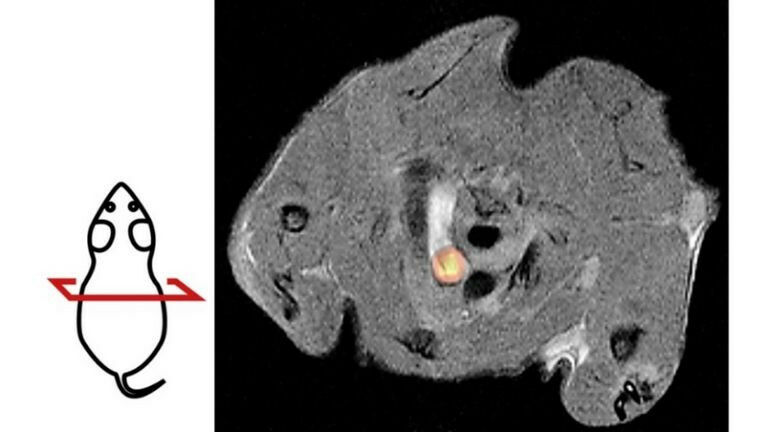

PET/MRI image of a mouse with atherosclerosis. The cross-sectional image shows the aortic arch as a bright structure in the center. The yellow glowing region represents an accumulation of potentially dangerous vascu-lar muscle cells. The drawing on the left illustrates the sectional plane of the PET/MRI image.

PET/MRI image of a mouse with atherosclerosis. The cross-sectional image shows the aortic arch as a bright structure in the center. The yellow glowing region represents an accumulation of potentially dangerous vascu-lar muscle cells. The drawing on the left illustrates the sectional plane of the PET/MRI image. Researchers at the University of Tübingen have developed a new method to better study atheroscle-rosis in mice. The non-invasive imaging method helps to better understand and treat narrowing of blood vessels, a cause of heart attacks and strokes. The new approach may also significantly reduce the number of animals used in experiments compared to previous methods.